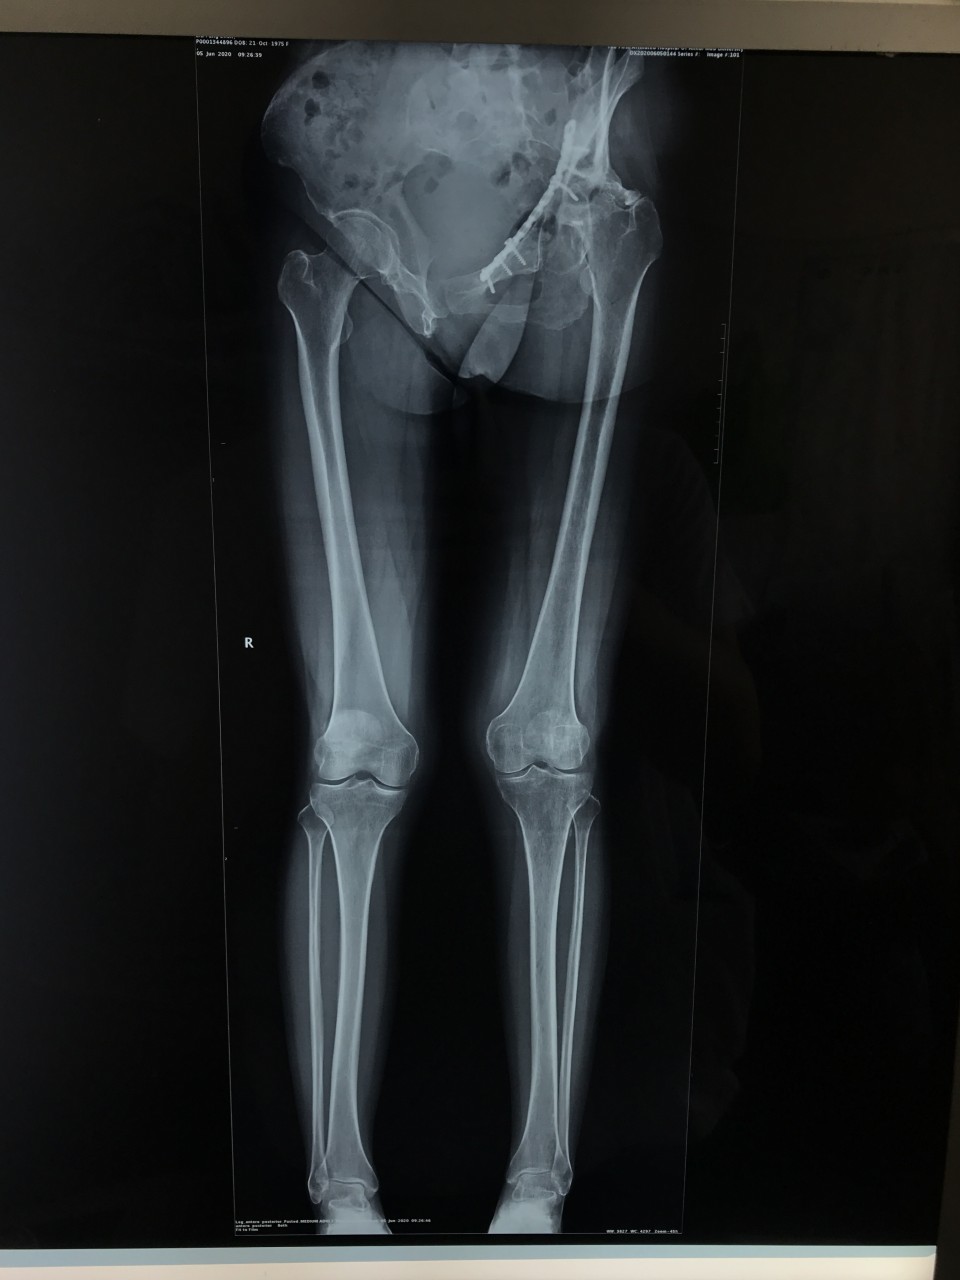

一位44岁女性患者因“左侧骨盆骨折术后疼痛伴渗液8年”入院。患者8年前因左侧骨盆骨折请上海专家行手术治疗,术后恢复不佳,髋关节感染,当地医生将部分钢板取出,残留的钢板因风险极大未予以处理。由于手术不彻底,伤口继续流脓,股骨头坏死,关节疼痛严重。因为手术风险极大,失败率高,多家医院拒收,患者慕名来到我院关节与显微修复外科胡孔足主任专家门诊,胡主任综合考虑各方因素以及现阶段我院的诊疗技术,将患者收治入院予以手术。术前结合患者病史,体检及辅助检查,反复讨论,制定了精细的手术方案,于6月10日,成功行一期手术,取出感染发炎的钢板,植入抗生素占位器。因为钢板和血管神经紧紧粘连在一起,稍有不注意就可能导致大出血,瘫痪、心跳骤停等严重后果。术后培养提示为MRSA,经过两个月规范抗感染治疗,培养提示阴性,未见细菌,感染消失。8月12日,胡主任顺利完成二期手术,“左侧全髋关节置换术”,目前手术后4天,患者已经能够扶拐下地行走,恢复良好,不久将康复出院。